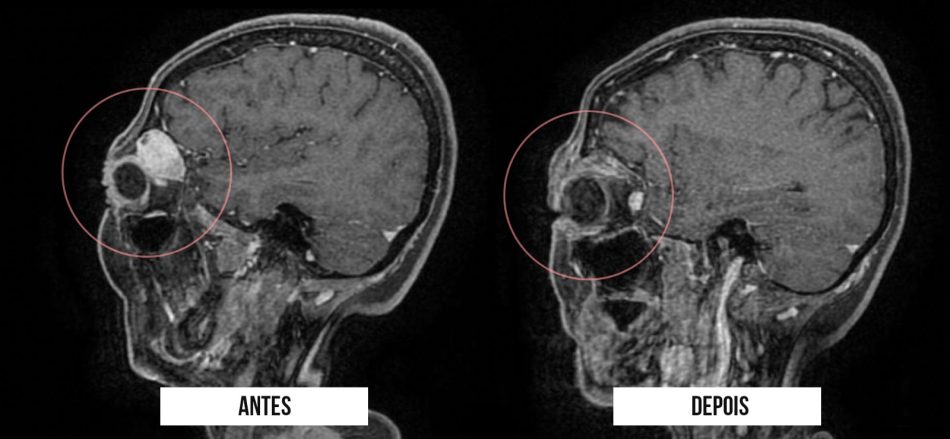

O Hospital Metropolitano Dom José Maria Pires – unidade pertencente à rede de saúde do Governo da Paraíba e gerenciado pela Fundação Paraibana de Gestão em Saúde (PB Saúde) – realizou através da equipe de neurocirurgiões a remoção de um tumor orbitário (região da órbita ocular, que trata-se da cavidade anterior do crânio), em uma paciente de 55 anos, do município de Sousa, sertão da Paraíba. No procedimento exitoso, foi utilizado pela primeira vez a técnica endoscópica transorbitária, minimamente invasiva, que evita a abertura do crânio, e possibilita uma recuperação célere ao paciente.

De acordo com o neurocirurgião responsável pelo caso, Breno Câmara, a técnica inovadora substitui a maneira convencional de retirada deste tipo de tumor, que é através de uma craniotomia, procedimento incisivo no couro cabeludo que pode trazer problemas funcionais e estéticos. “Utilizando o endoscópio de base de crânio, realizamos uma pequena incisão de menos de 3 centímetros na pálpebra superior da paciente o que possibilitou a visualização do campo cirúrgico através do endoscópio, e desse modo fizemos toda a remoção, com a garantia de trauma cirúrgico mínimo e com possibilidade de alta hospitalar em 48h”, destacou, o especialista em tumores de base de crânio.

Mais sobre a patologia e tratamento – Trata-se de um tumor intraorbitário. A órbita é o arcabouço ósseo onde repousam o globo ocular e seus anexos (músculos, nervos, glândulas lacrimais, vasos sanguíneos e gordura). Esta estrutura possui formato de cone, é composta por 7 ossos do crânio, relacionados com a face e também com a base do crânio. O tumor causava cefaléia (dor de cabeça), proptose (projeção do globo ocular com assimetria das órbitas) e perda da acuidade visual à direita, na paciente. Tendo sido realizado de forma pioneira para o tratamento a técnica endoscópica transorbitária.